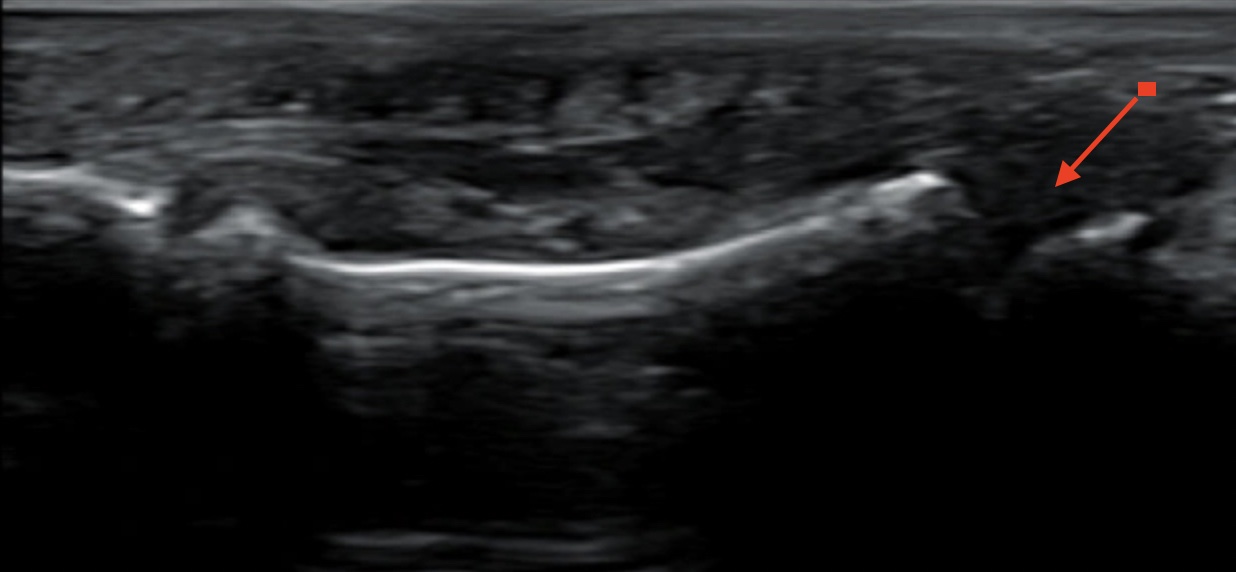

Hallazgos ecográficos

Ecografía portátil: Pérdida ósea de la cortical en falange distal del dedo afecto (segundo de la mano derecha).